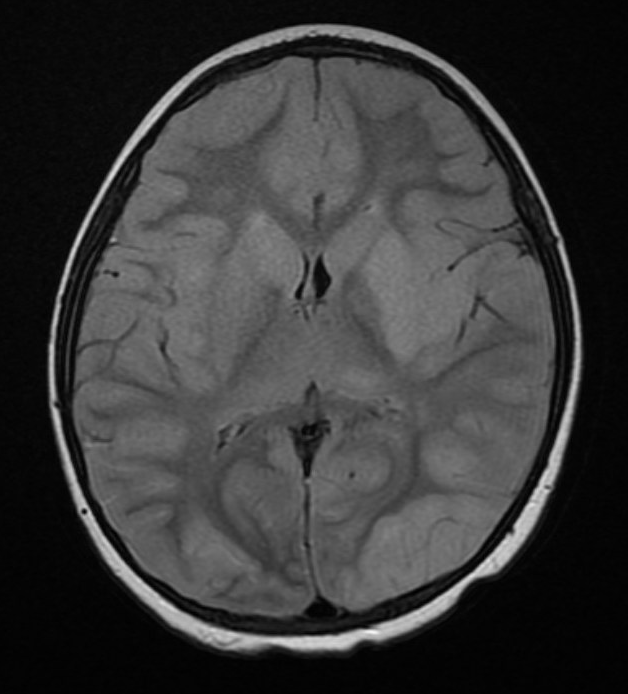

MRI T2 FLAIR.png